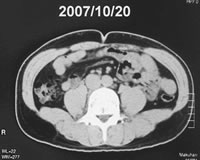

| 図5 治療前後の推移(腹部CT) 千葉健生病院放射線科 佐藤元氏計測 |

||||||||||||||

![]() |

⇒ | ![]() |

||||||||||||

◆上のへこみがおへそ。黒く見える部分が脂肪。7カ月で脂肪はほぼ半減 |